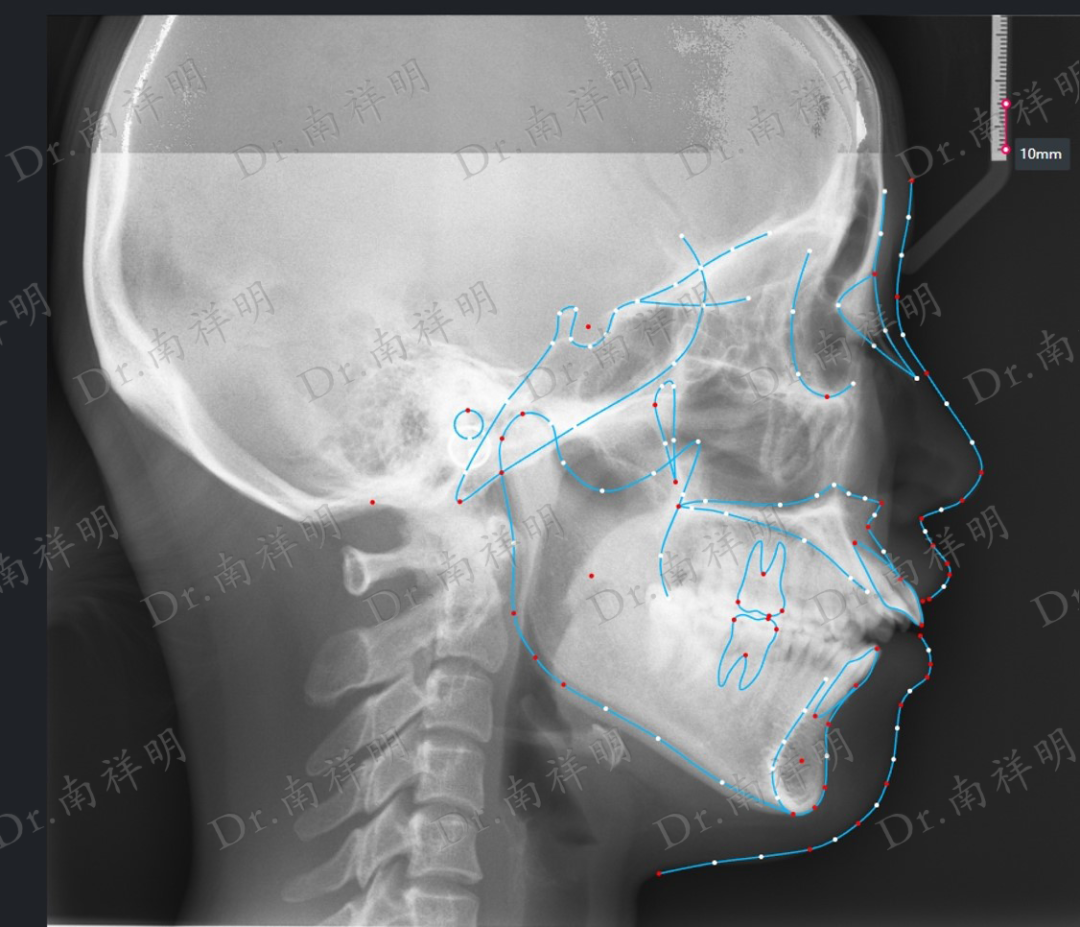

X线检查

全景位片分析:

双侧髁突基本对称,骨皮质清晰连续

牙槽骨内未见明显异常

18缺失,28、38、48正位萌出

双侧下颌升支长度基本协调

诊断

牙型:Angle II类

骨型:骨性I类 高角

面型:凸面型

问题列表

1.牙 列:上牙列轻度拥挤,下牙列中度拥挤

2.横 向:上下基骨基本正常,上后牙稍内倾

3.失状向:下颌顺时针旋转

4.垂直向:高角 上颌后牙垂直生长过度 下前牙压槽高度不足

5.软组织:上唇肌张力不足

6.肌肉:吞咽、发音伸舌习惯